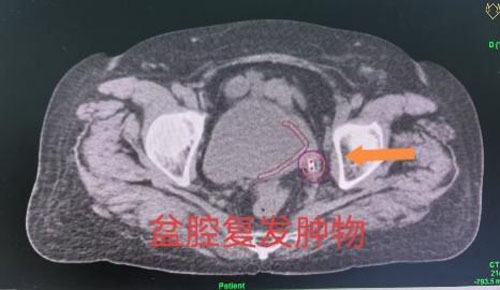

劉紅教授和婦產超聲科王翠菊教授團隊為來訪專家展示了兩例疑難病例插植放療操作的全過程。一名患者為宮頸癌IIIC1R期盆腔閉孔區域淋巴結轉移。淋巴結轉移是宮頸癌最常見的轉移路徑,同時也是影響宮頸癌患者預后最主要的危險因素之一,轉移淋巴結通常需要更高的放療劑量才能獲得更好的局部控制效果。通過該項技術,在后裝治療過程中可以同時實現宮頸腫物和轉移淋巴結的同步推量照射,在保護危及器官的同時,給予轉移淋巴結更高的放射劑量,從而獲得更好的腫瘤局部控制效果。另一名患者為宮頸癌術后膀胱后壁腫物復發。腫物體積越小,治療效果越好,放療的副損傷越小,但是,體積越小的腫物越難做到精準插植治療。經腔內超聲實時引導的插植技術,可以實現對微小腫物的精準定位,在確保不損傷膀胱的前提下,精準實現盆腔復發腫物的近距離放療。